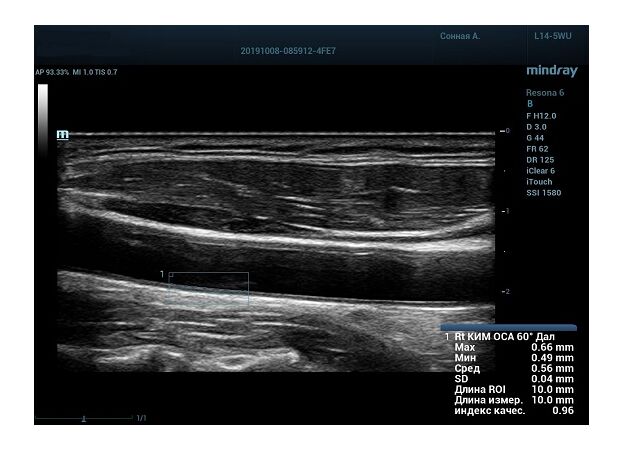

На сегодняшний день измерение IMT происходит автоматическим путем при использовании функции AUTO-IMT. Необходимо указать прибору зону интереса, стандартной длиной (1 см), в которой происходит отслеживание кромок и выдача максимального, среднего и минимального значения. УЗИ аппараты компании Mindray среднего, экспертного и премиального класса снабжены данной функцией и позволяют контролировать не только полученные значения, но и оценить точность измерения кромки в конкретной зоне по индексу качества. Используя индекс качества, легко решить, можно ли использовать полученное значение.

Форма отчета стала удобной: в единой таблице сводятся измерения левых и правых артерий, указываются все значения с автоматическим расчетом общего среднего показателя. Если один из показателей измерения резко выбивается и считается недостоверным – его можно исключить из расчета.